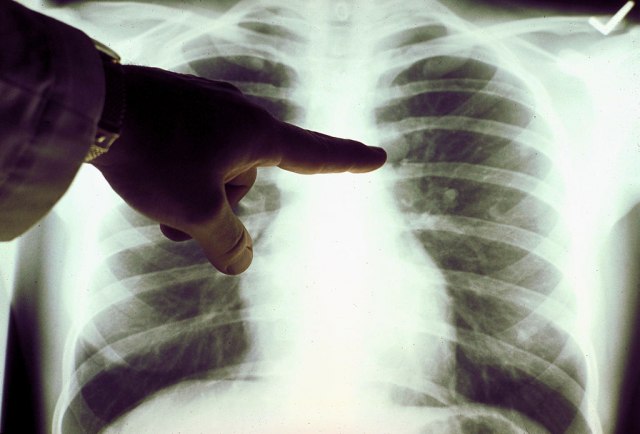

Konzumiranje jogurta i namirnica bogatih vlaknima povezuje se sa smanjenim rizikom od razvoja raka pluća, pokazali su rezultati nove američke studije.